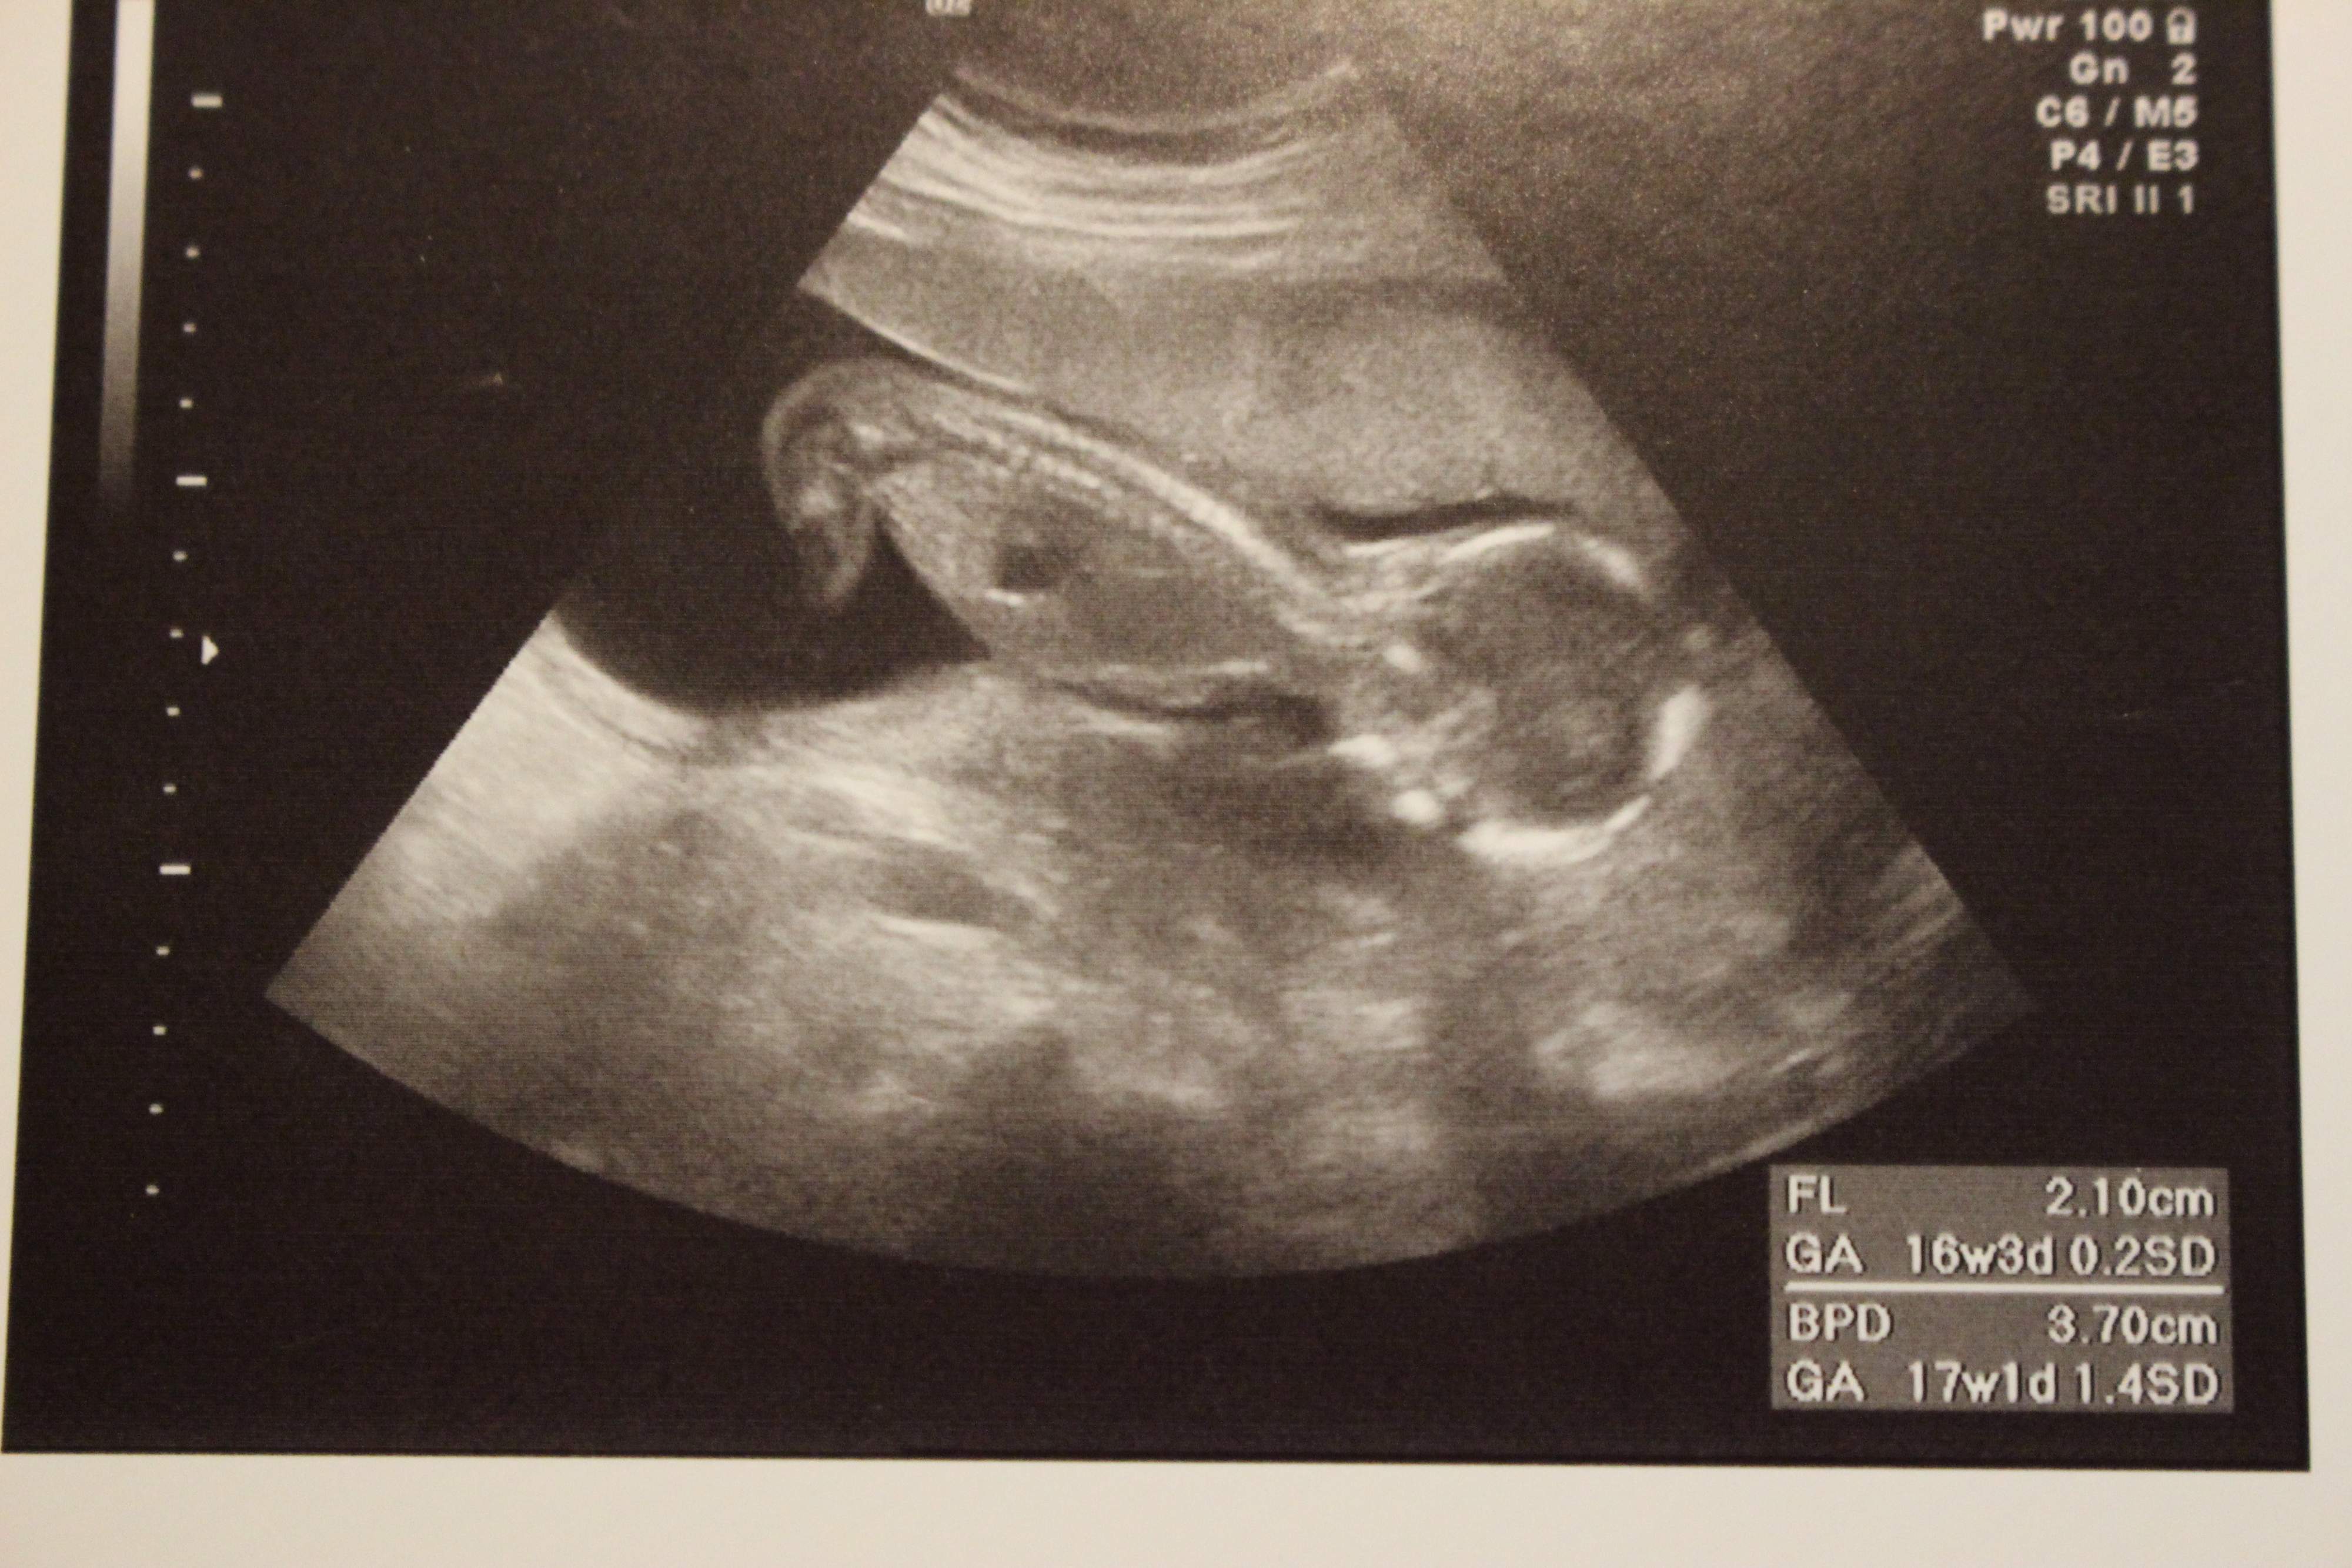

妊娠17週目のエコー写真

産科のある病院に転院して最初に撮ったエコー写真です。これまでの写真と比べても、よく動き回っているのが分かります。赤ちゃんの首の後ろにあるむくみ部分の厚みにも、問題無さそうとの見解でした